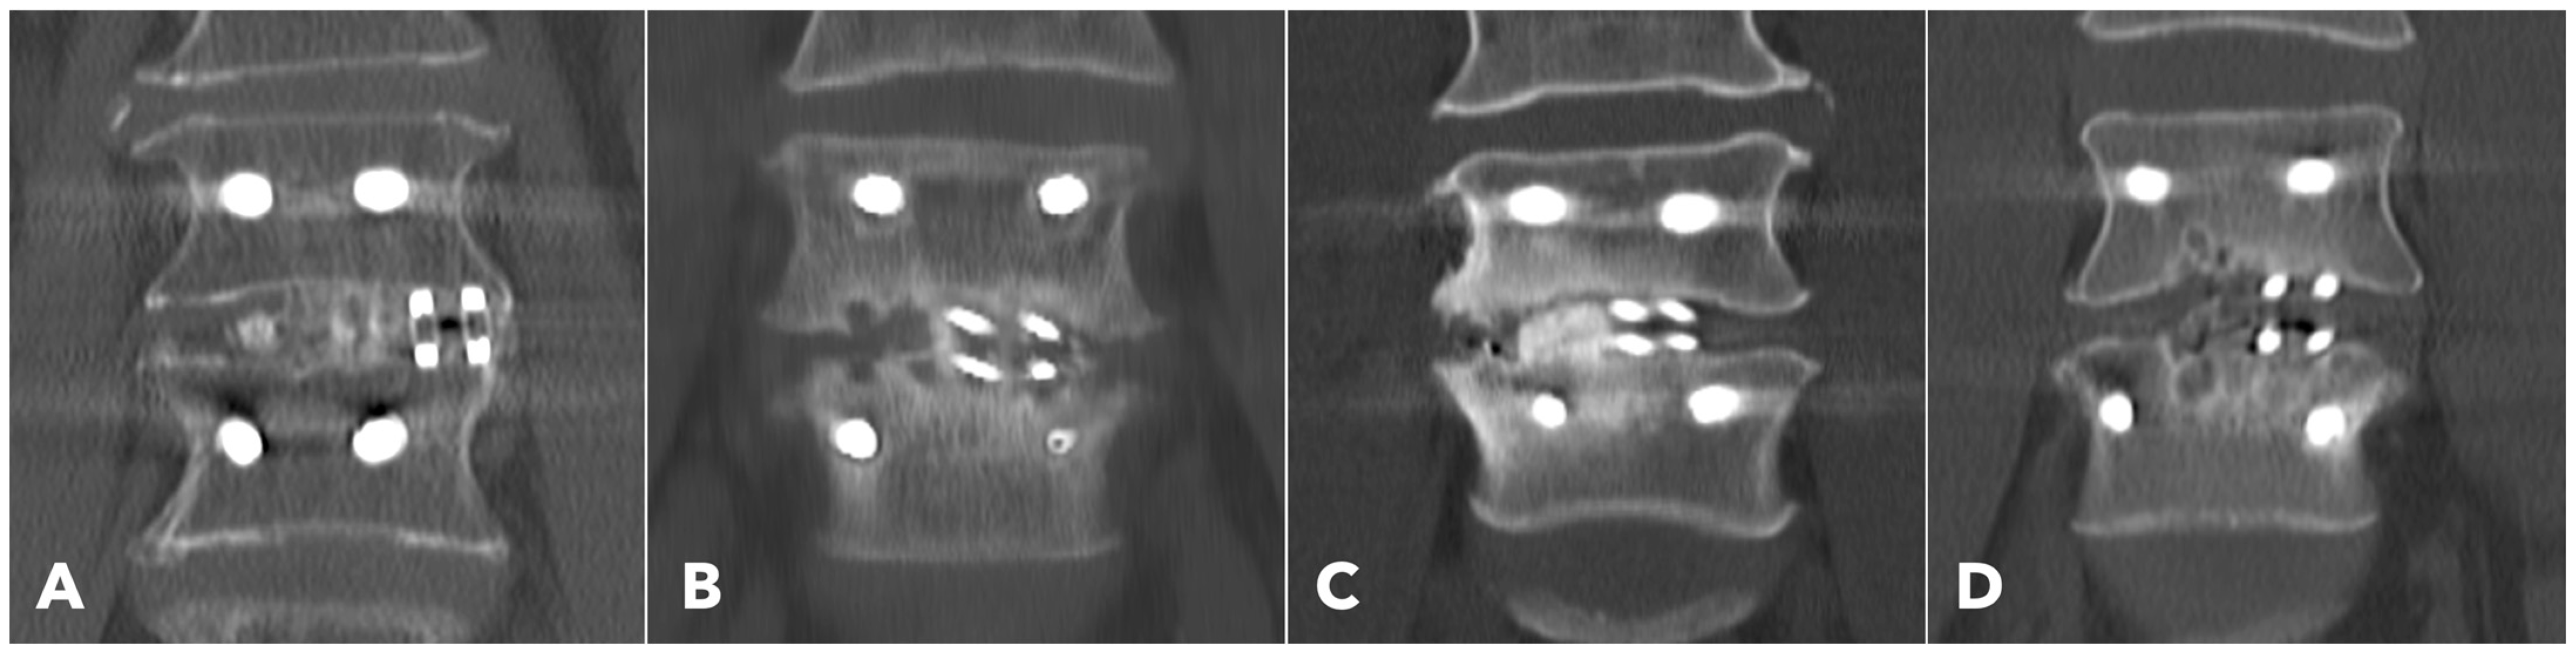

Lumbar spine computed tomography (CT) with 3 mm thin-slice coronal and sagittal reconstructions was performed one year after the surgery. Fusion status was assessed using the Bridwell grading system based on bone window images (Figure 4). Grades I and II were defined as successful fusion. Cage subsidence was defined as sinking > 2 mm beyond the bony endplate [24,30]. The presence of subchondral osteolysis was also recorded as a potential indicator of pseudoarthrosis (Figure 5).

Subchondral osteolysis was significantly more frequent in the MISTLIF group (52.9% vs. 13.3%, q < 0.001). Cage subsidence was also significantly more prevalent in the MISTLIF group (13.7% vs. 5.0%, p = 0.023), although most patients in both groups exhibited no evidence of subsidence (Table 5). Again, the statistical significance was no longer significant after applying the Benjamini–Hochberg correction to control the FDR.

Figure 5. (A,B) 1-year CT reconstruction revealed the presence of subchondral osteolysis or endplate cyst formation (white arrowheads). (C) The measurement of cage subsidence on the coronal CT reconstruction image.